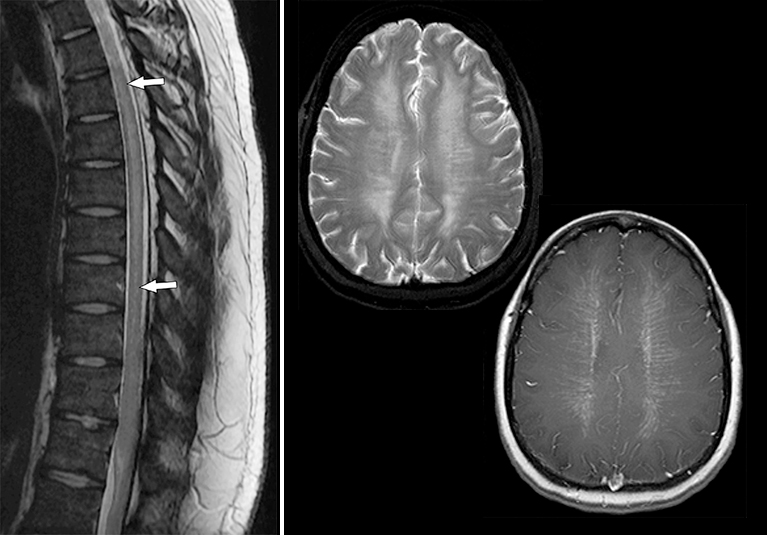

From epos.myesr.org